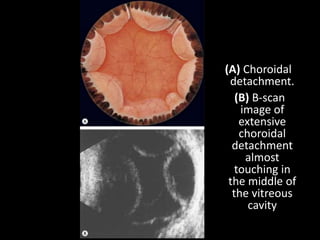

Choroidal detachment

1 Symptoms. Photopsia and floaters are absent

A visual field defect may be noticed if the choroidal

detachment is extensive.

2 Signs

• Low intraocular pressure is common as a result of

concomitant detachment of the ciliary body.

• The anterior chamber may be shallow in eyes with

extensive choroidal detachments.

• The elevations are brown, convex, smooth and

relatively immobile.

• • Large ‘kissing’ choroidal detachments may

obscure the view of the fundus.

• The elevations do not extend to the posterior

pole because they are limited by the firm adhesion

between the suprachoroidal lamellae where the

vortex veins enter their scleral canals.

(A) Choroidal

detachment.

(B) B-scan

image of

extensive

choroidal

detachment

almost

touching in

the middle of

the vitreous

cavity